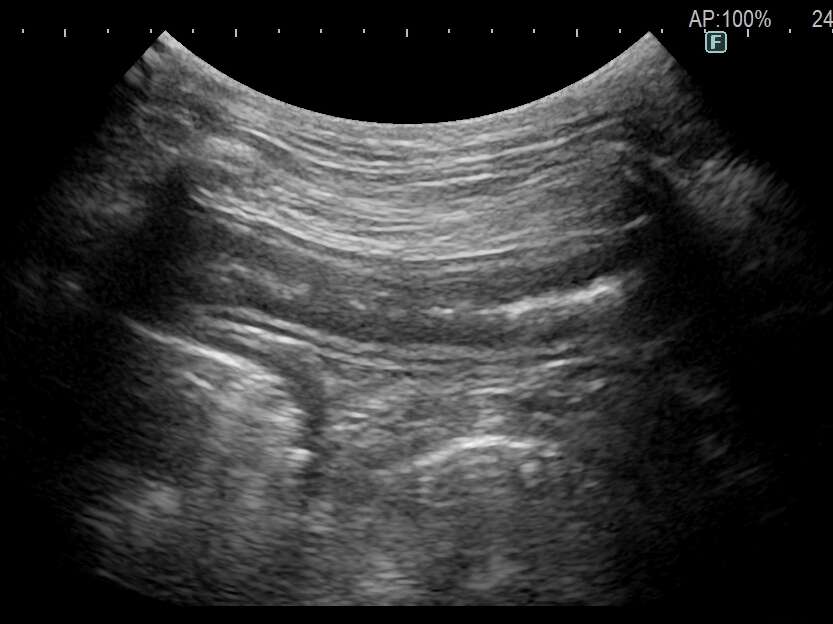

拡張の乏しい(正常に近い)消化管の様子